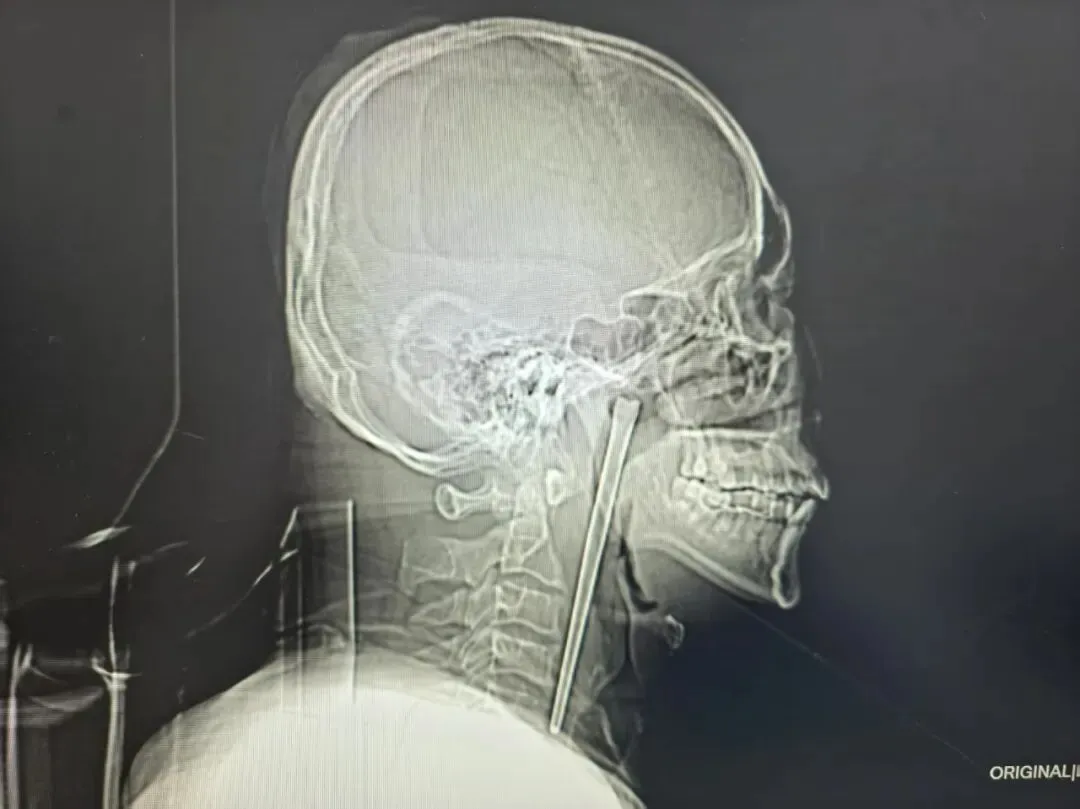

Житель міста Далянь у провінції Ляонін восьмий рік жив із металевою паличкою для їжі довжиною 12 см, що застрягла в його горлі. Цей випадок привертає увагу через незвичайне ставлення чоловіка до проблеми і тривалий час приховування травми.

Чоловік на прізвище Ван випадково проковтнув паличку під час їжі та вживання алкоголю. Він відчув біль, але у нього не виникли ускладнення з диханням, а голосові зв’язки працювали нормально. Проте Ван відмовився від операції через страх перед хірургічним втручанням із розрізом на шиї.

В анкеті хворого також зазначено залежність від алкоголю, він пояснював дискомфорт у горлі як «звичайну реакцію» організму на спиртне. Лише цього року, коли больові відчуття значно посилилися, він звернувся до лікарні. Медики виявили паличку в області м’якого піднебіння, але без пошкоджень життєво важливих органів.

Паличку вилучили малоінвазивним методом через рот, операція пройшла успішно. Цей випадок демонструє, наскільки важливо не ігнорувати симптоми і своєчасно звертатися за медичною допомогою, навіть якщо страх перед операцією змушує людину мовчати.